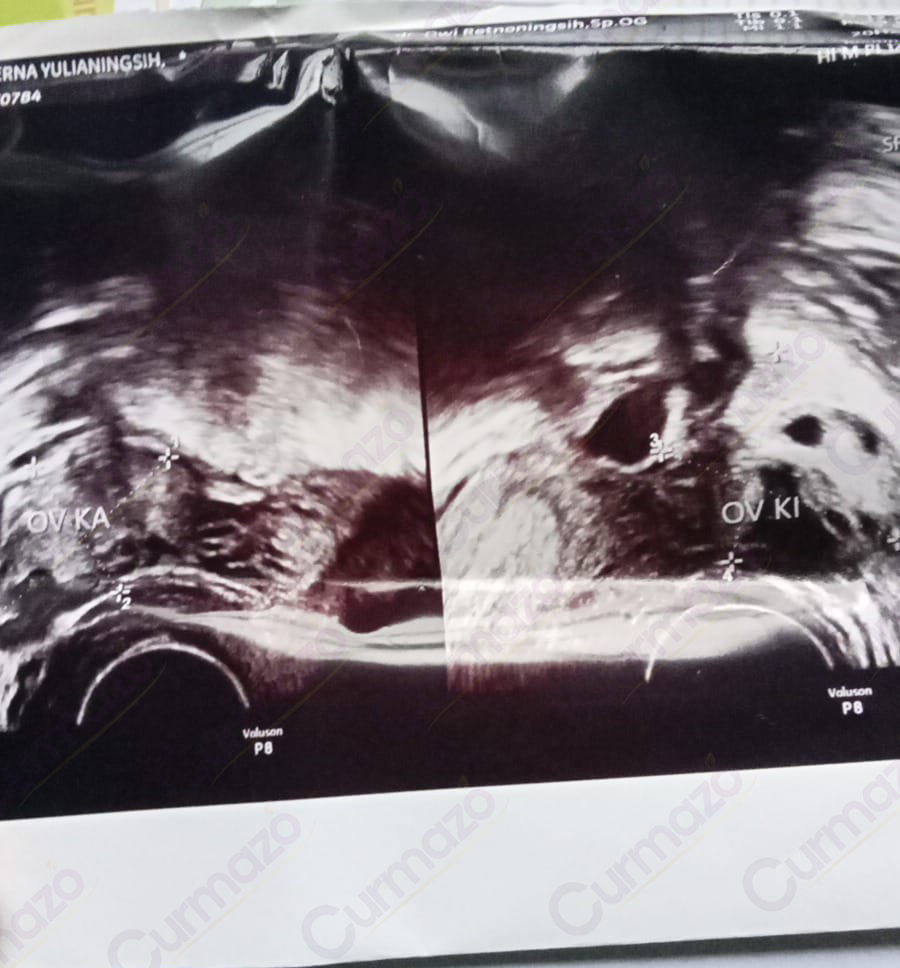

25 Agustus 2025, setelah pulang kerja badan saya rasanya capek sekali dan perut bagian bawah terasa nyeri, akhirnya saya pergi cek ke dokter kandungan. Saya kaget sama hasil USG nya. Ternyata saya ada 3 kista yang berukuran 5.59 cm, 4.68 cm, dan 5.23 cm. Disitu saya baru paham, ternyata gejala yang selama ini saya alami itu disebabkan oleh kista.

Foto hasil USG before:

Tanggal 5 Oktober 2025 saya USG di dokter yang sama, dokter kaget lihat kista saya sudah tidak ada. Sebelumnya saya juga tidak menyangka kalau hilang total, pikir saya kalo mengecil aja udah alhamdulillah banget tapi justru hilang total. Dokter juga gak nyangka, akhirnya USG lagi sampai 3 kali. Namun, hasilnya tetap sama saja 3 kista sudah tidak ada yang berarti hilang total!

Foto hasil USG after: